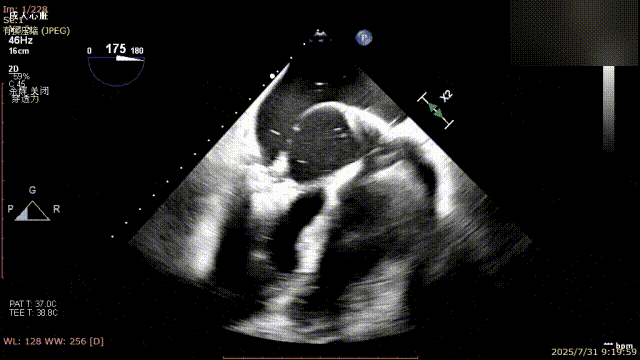

手术过程中,麻醉与围术期医学科副主任医师马金本确保麻醉过程平稳。心脏大血管外科主治医师董明亮穿刺股静脉置入血管鞘,并在心脏超声科梁皓主任及段福建教授TEE引导下,顺利穿刺房间隔,房间隔穿刺高度4.9cm。随后,在王安彪主任以及刘洋教授指导、心脏超声科梁皓主任TEE引导下,董明亮医师沿输送系统将延展呈“一字型”状态的国产夹合器送至左房,缓慢关闭夹合器并进行弹道测试。调整夹合器位置和方向后,董明亮医师再次将夹合器延展呈“一字型”完成跨瓣,避免发生腱索缠绕,成功捕获瓣叶后关闭夹合器,二尖瓣反流显著下降。夹合器完全解离后,超声示二尖瓣反流程度显著下降,残余反流0,平均跨瓣压差1mmHg,手术圆满成功。

房间隔穿刺

夹合器“一字型”状态进入左房

缓慢关闭夹合器

捕获瓣叶并放下Gripper

关闭夹合器